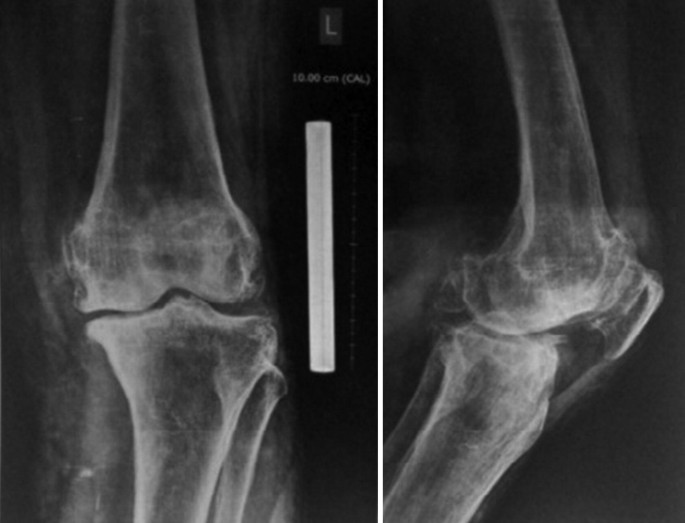

2. آرتروز (ساییدگی مفصل): شایع‌ترین در زانو، لگن و ستون فقرات

مشکل آرتروز